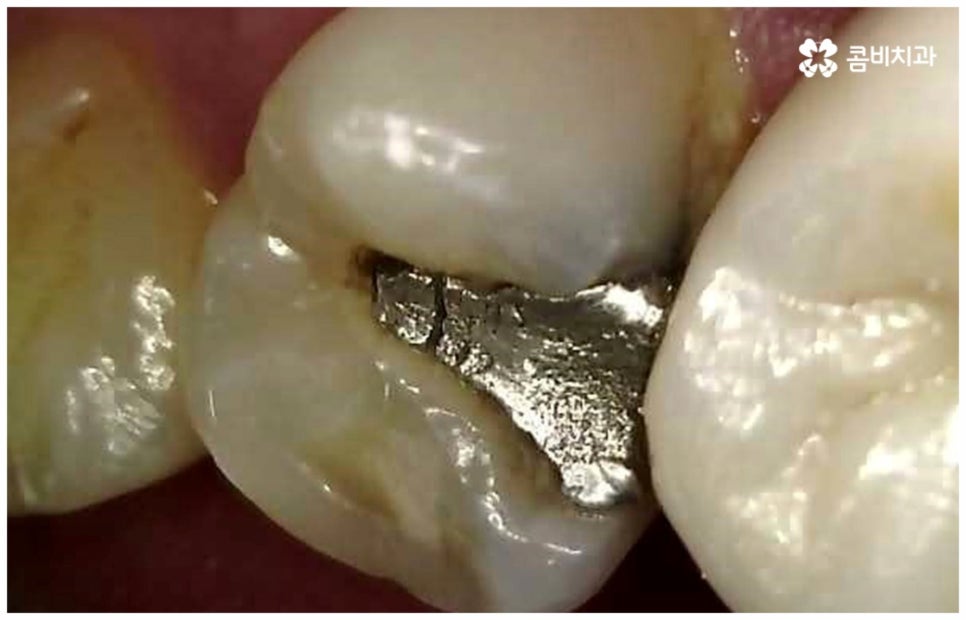

법랑질 안 쪽의 상아질이 손상되면 치아가 시린 증상이 점점 심해지며 이후로 병증도 더 빠르게 악화될 수 있기 때문에 예전보다 불편함을 자주 느끼게 되었다면 치료를 서둘러야 하는데 초기에는 치아 손상 부위를 제거하고 레진으로 직접 때웠다면 이때는 인레이 또는 온레이처럼 본을 떠서 만든 보철물을 끼워넣는 간접적인 방법으로 충치 치료를 할 수 있어요. 특히 보철물을 선택할 때는 환자분들의 상황을 고려하여 치아의 위치 및 역할에 적합한 재질을 이용하게 되는데 보통 입을 벌렸을 때 잘 보이는 앞니는 심미성을 좀 더 중시하게 되고 어금니는 강한 저작력을 견딜 수 있는 내구성을 중시하고 있는데요.

옛날에는 어금니 보철물로 금을 많이 사용했었어요. 금은 잘 부러지지 않고 얇게 늘어나는 성질을 가지고 있기 때문에 치아를 많이 삭제하지 않고도 원하는 모양대로 정확하게 보철물을 만들 수 있으며 압력이나 교합 등 대합치와의 적응 역시 보다 빠르고 적절하게 이뤄질 수 있다는 점에서 아주 오래 전부터 보철물 재료로 사용되어 왔어요. 그러나 치아 색상과 너무 다르기 때문에 눈에 잘 띄인다는 점 (특히 아래 어금니는 입을 크게 벌렸을 때 보이는 위치라서 심미적으로 좋지 않을 수 있음) 그리고 온도 자극을 잘 전달하는 편이므로 어금니신경치료 를 하지 않은 치아의 경우 불편함을 느낄 수 있다는 점 때문에 요즘은 치아 색상 재질 중에 강도와 내구성이 강한 지르코니아 재질을 많이 이용하고 있어요.